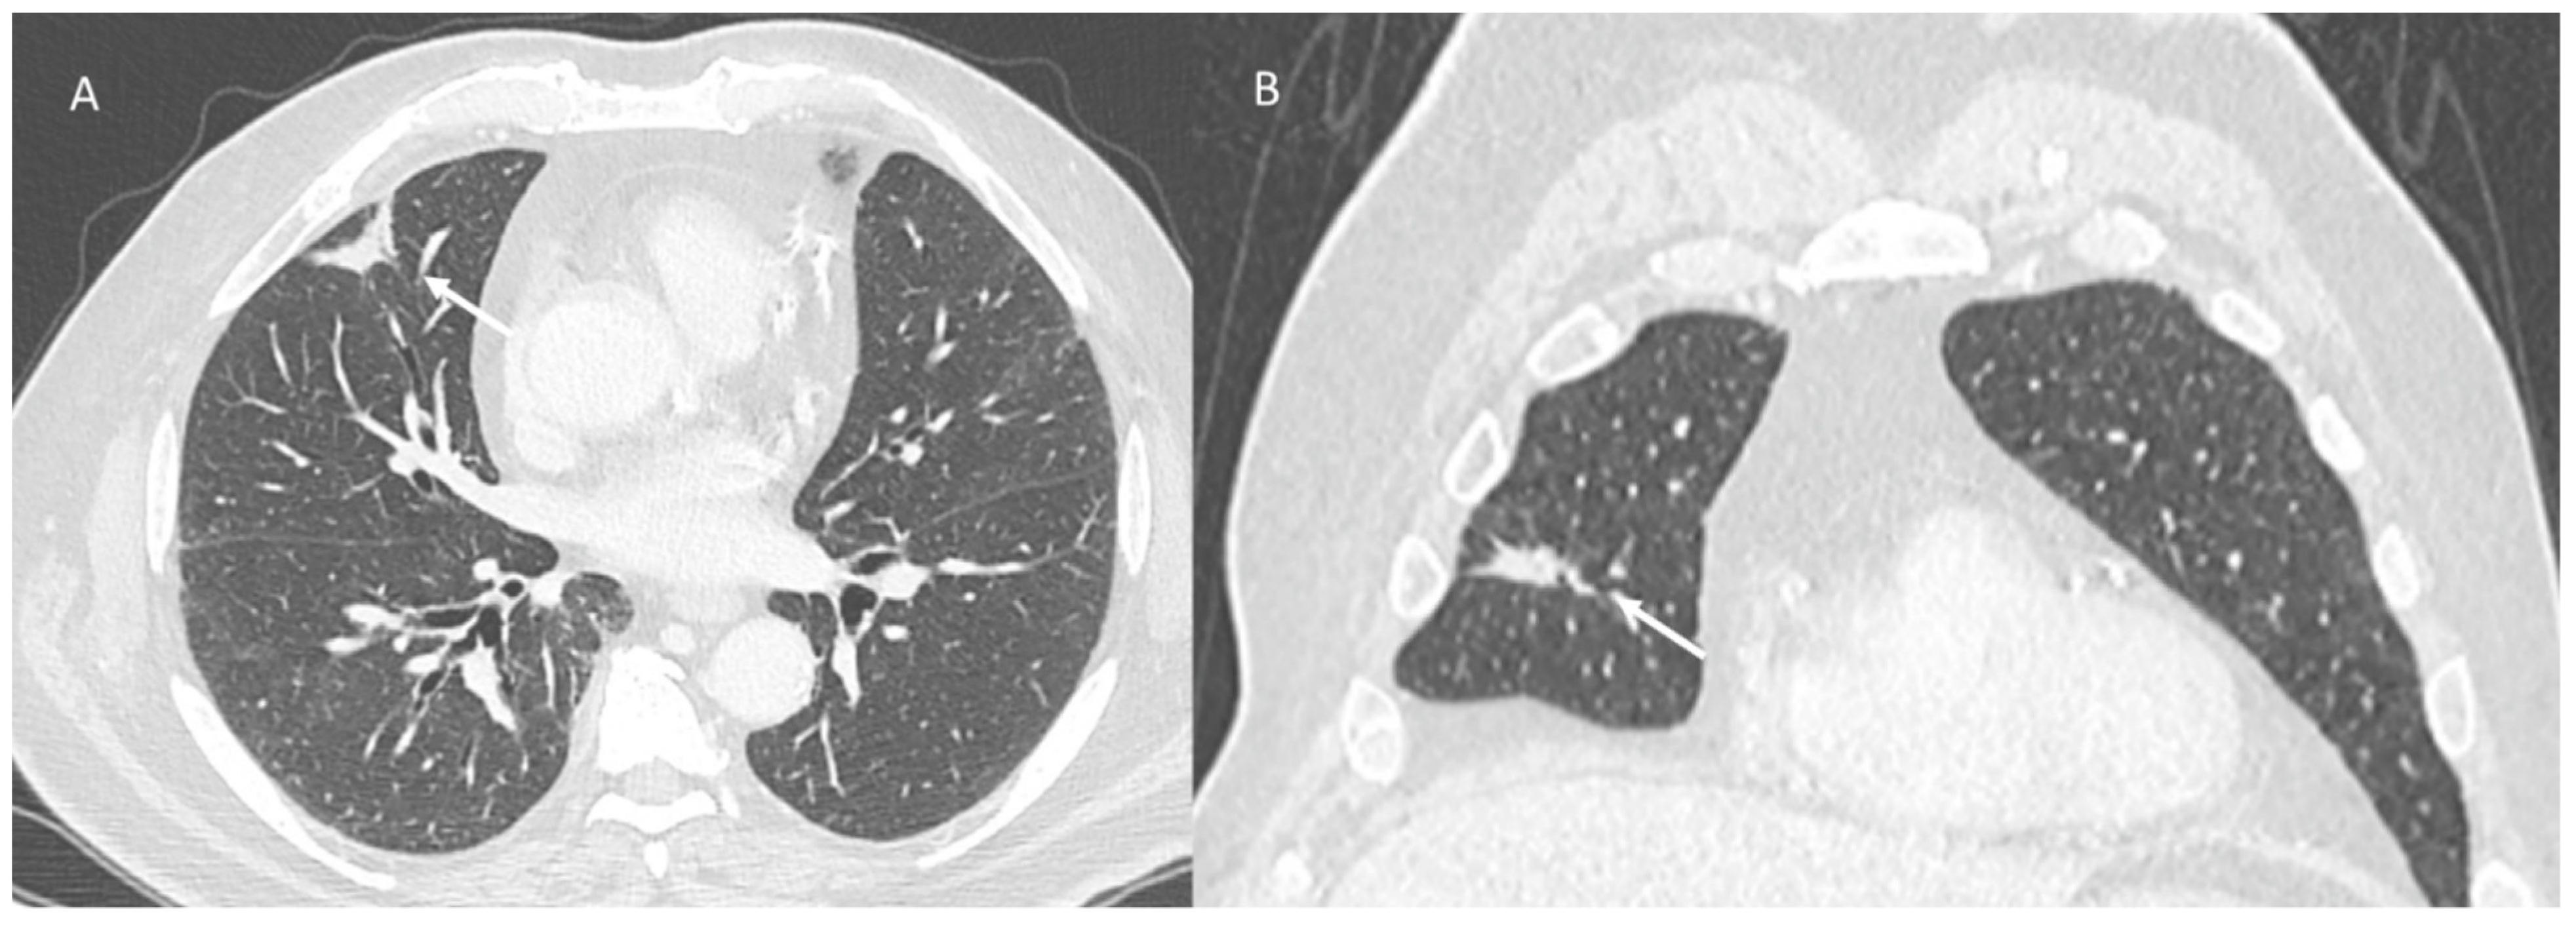

Pulmonary lymphangitis carcinomatosa (PLC) is an unusual appearance of metastatic lung disease in which advanced cancers spread through pulmonary lymphatic vessels (Figure 1).

Imaging has low specificity for PLC detection because images are often normal in initial phases. However, imaging is often performed to rule out other causes [57,78,79,80,81,82,83,84,85]. A chest radiograph (chest X-ray) may be the first approach and an association of several radiological findings could favour the diagnosis in about half the cases. However, in 30 to 50% of patients, especially in the initial phases, the X-ray may be normal [56,57]. Therefore, computed tomography (CT) and especially high-resolution CT (HRCT) are recommended techniques for studying patients with suspected PLC [55,56,57,86,87,88,89,90,91,92,93]. The CT results are similar to other interstitial lung diseases, so they have low diagnostic accuracy in differentiating and detecting PLC [56,57]. The usual CT findings comprise nodular or diffuse intrapulmonary infiltrates, irregularly interlobular septal thickening, smooth (early stage) or nodular thickening (late development), hilar and mediastinal lymphadenopathy, ground-glass opacity due to interstitial oedema or parenchymal extension of tumours, and pleural effusions. These features could be on one or both sides, focal or diffuse, or symmetrical or asymmetrical. Smooth or irregularly thickened interlobular septae are more conducive to PLC than to tumour embolism. Although nodular thickening of the septae is thought to differentiate PLC from other interstitial lung patterns, some conditions such as sarcoidosis or asbestosis may mimic it [57]. Another distinguishing feature of PLC is the preservation of the general and lobular architecture of the lung. [56,57].

Figure 1. PLC in pancreatic cancer patient. CT (axial (A,C) and coronal (B,D)) shows comprise diffuse intrapulmonary infiltrates (arrows) with irregularly interlobular septal thickening, nodular thickening and pleural effusions.